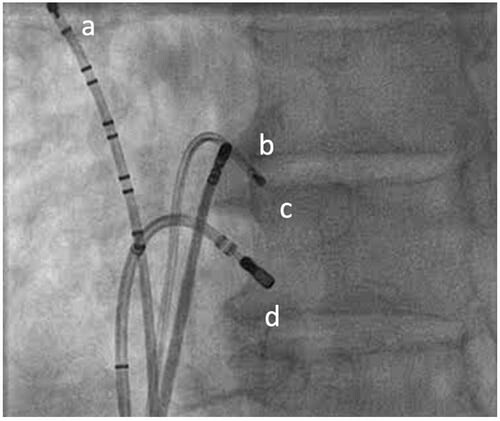

Nach ausgedehntem konventionellem Mapping am Trikuspidalring kann bei frühester Aktivierung rechtsatrial, posteroseptal mittels 8 mm F-Kurve die akzessorische Bahn erfolgreich lokalisiert (Abbildung 4) und mit RF-Strom abladiert werden, max. 60 W ungekühlt , max. 80 Sekunden, gesamt 1100 Sekunden.

Abbildung4

Abbildung 4: Abblationsposition rechts posteroseptal in LAO (d). Mehrpoliger diagnostischer Katheter in HRA-Position (a), HIS-Position (b), RV (c)